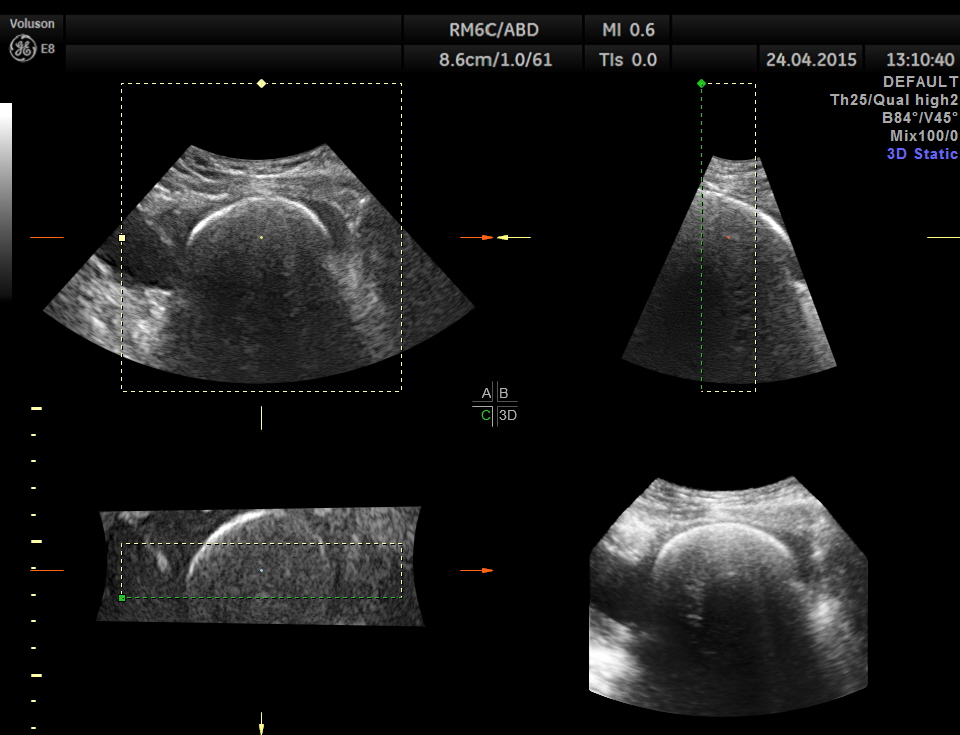

Scan of the urinary bladder in a more cephalic angle shows the following :

A large calcification in the urinary bladder – ? large urinary bladder stone , calcified median lobe of the prostate, or a calcified mass within the bladder .

3D tweaking looks more like a large stone.

Superior angling shows a multi cystic pelvic mass – ? bladder diverticulae